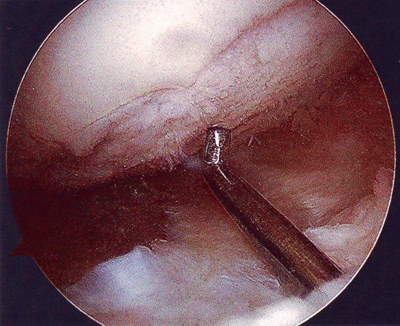

Moni miettii, miltäköhän tuon polven sisällä näyttää? Se selviää vilkaisemalla alla olevia kuvia!

Vasemmanpuoleinen kuva kertoo syvällä olleesta sisäkierukan repeämästä. Oikeanpuoleinen kuva on sisäreiden rustokulumasta, vaikka ei tämmöisellä hyvällä hevosella voi mitään kulumia olla!